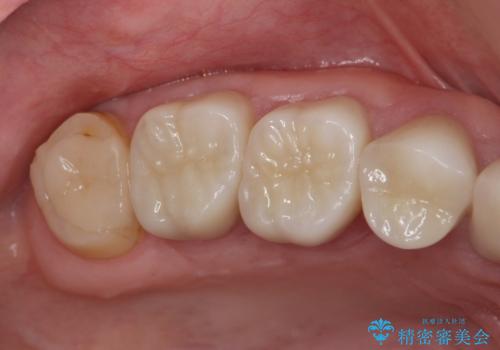

歯周外科で達成する安定したクラウン周囲の歯肉環境

- 重度の歯ぎしり癖で歯がすり減り、見た目・噛み合わせの改善とこれ以上すり減る前の処置を希望され来院されました。

高さが短くなってしまった歯は、安定したクラウンを作るのが難しいため歯ぐきを下げる歯周外科を行ったのちに強度に優れるフルジルコニアクラウンで補綴治療を行います。

すり減ってしまった歯に対し、歯冠長延長術(歯周外科)を行うことで安定したクラウンを製作・装着することが出来ました。